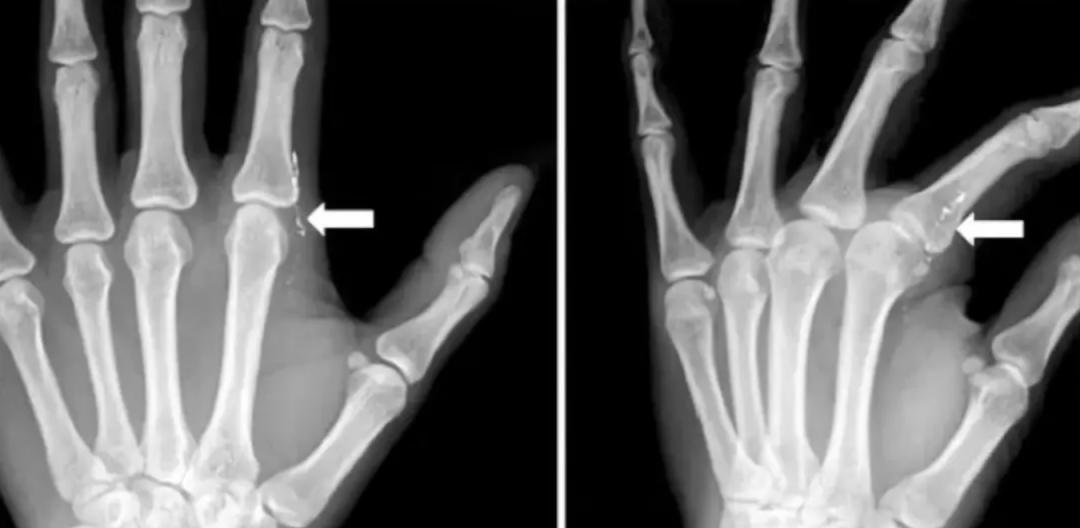

J Hand Surg Asian Pac 曾发表过这样一个病例:

一名 42 岁的妈妈去看病,觉得「左食指有异物感」。

医生追问病史了解到,她在 1 个月前在给女儿量体温时,不小心打碎水银温度计。清理体温计碎片的时候,左手指被刺伤,当时觉得没有大碍,就没有就诊。

医生发现,患者左手手指有肉芽组织,检验血液、尿液后发现,有汞中毒的迹象。

左食指第二掌指关节桡侧疼痛

▼

X 片可见皮下线状高密度影

最后手术切除的肉芽里

还有细小闪亮的水银滴